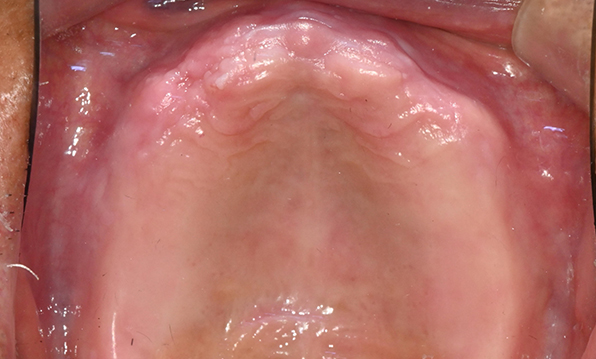

잇몸뼈가 얇은 상태

전체 임플란트를 해야하는 환자들은

대부분 고령의 환자들로 오랜 틀니 사용

또는 노화로 인해 치조골이

거의 남아있지 않는 경우가 많습니다.

이 때, 치조골 이식을 병행하여 잇몸뼈 재건 후 안정적인 임플란트 식립을 하고 있습니다.